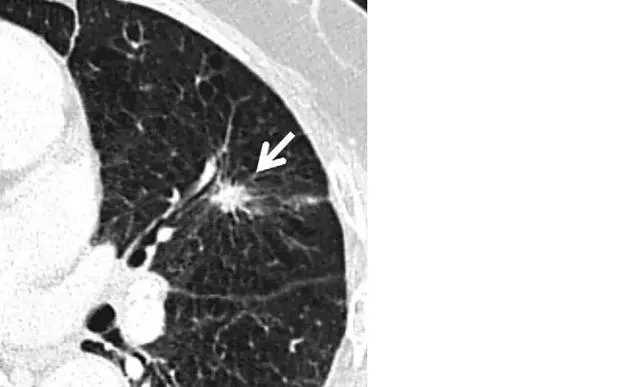

(3)结节边缘:恶性肺结节多呈分叶状,或有毛刺征(或称棘状突起),胸膜凹陷征及血管集束征常提示恶性的可能;良性肺结节多数无分叶,边缘可有尖角或纤维条索等,周围出现纤维条索、胸膜增厚等征象则常提示结节为良性;

左肺上叶层厚 1 mm 的 CT 横断面图像,显示一个可疑的实性毛刺状结节(箭头)。手术证实为浸润性腺癌。

根据外观判断良恶性是"以貌取人",尽管"分叶、毛刺、胸膜凹陷征"是恶性病变的特点,但由于小结节中的早期肺癌很少见到这些特点,所以同时需要内部特征协助鉴别诊断。